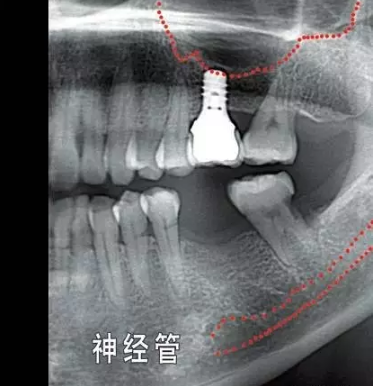

就種植手術(shù)本身而言,您頜面部一些重要結(jié)構(gòu)(例如下頜神經(jīng),上頜竇) 的位置和形態(tài)會增加手術(shù)風(fēng)險和操作難度,為避免因手術(shù)損傷這些重要結(jié)構(gòu),醫(yī)院會要求您手術(shù)前拍攝3D X光片作為參考,以便牙醫(yī)結(jié)合這些材料和您具體分析手術(shù)的風(fēng)險程度。